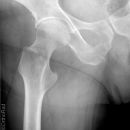

Cam FAI mit herniation pit